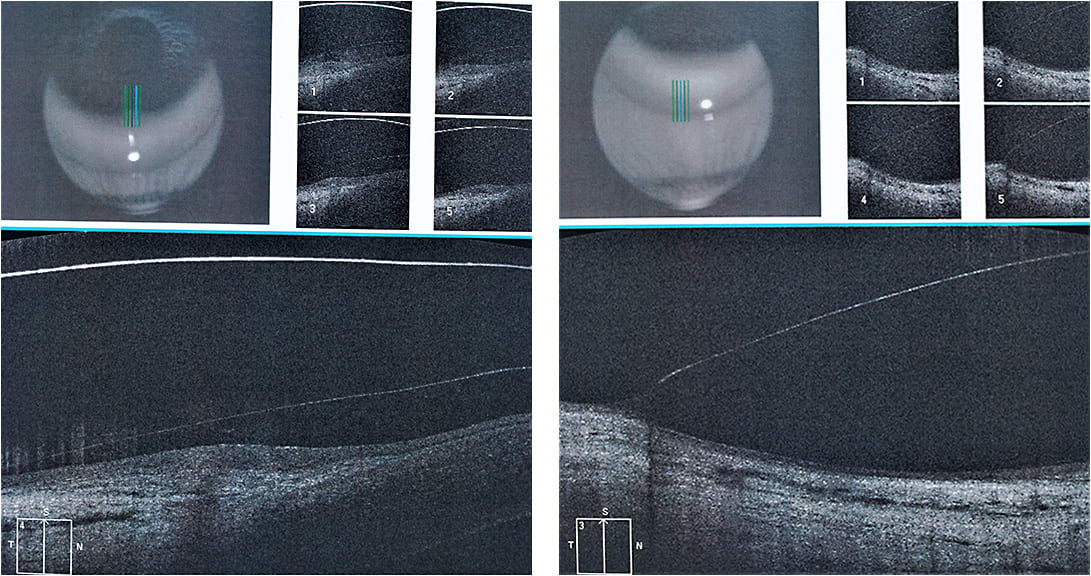

The 15.7mm scleral lens worked very well, especially with the modifications; the sag was ideal, and there was no touch at the limbus despite the really short landing zone due to a small haptic. This lens also centered better (Figure 5) compared to the 17.5mm and 16.5mm lenses.

The modifications made to the different angles over the sclera also helped to avoid excessive pressure or loose areas.

To maintain the desired vault over the cornea, we changed the base curve and secondary base curve to obtain the best possible alignment (Figure 6).

The anterior cornea OCT images were of great help to better estimate the necessary changes to the scleral lens designs (Figures 7 through 10). We started using this method a few years ago, but we use it only when necessary. Most of our scleral lens fits do not require OCT, as the scleral lens design that we typically fit has a slightly flatter haptic alignment horizontally compared to the vertical haptic.